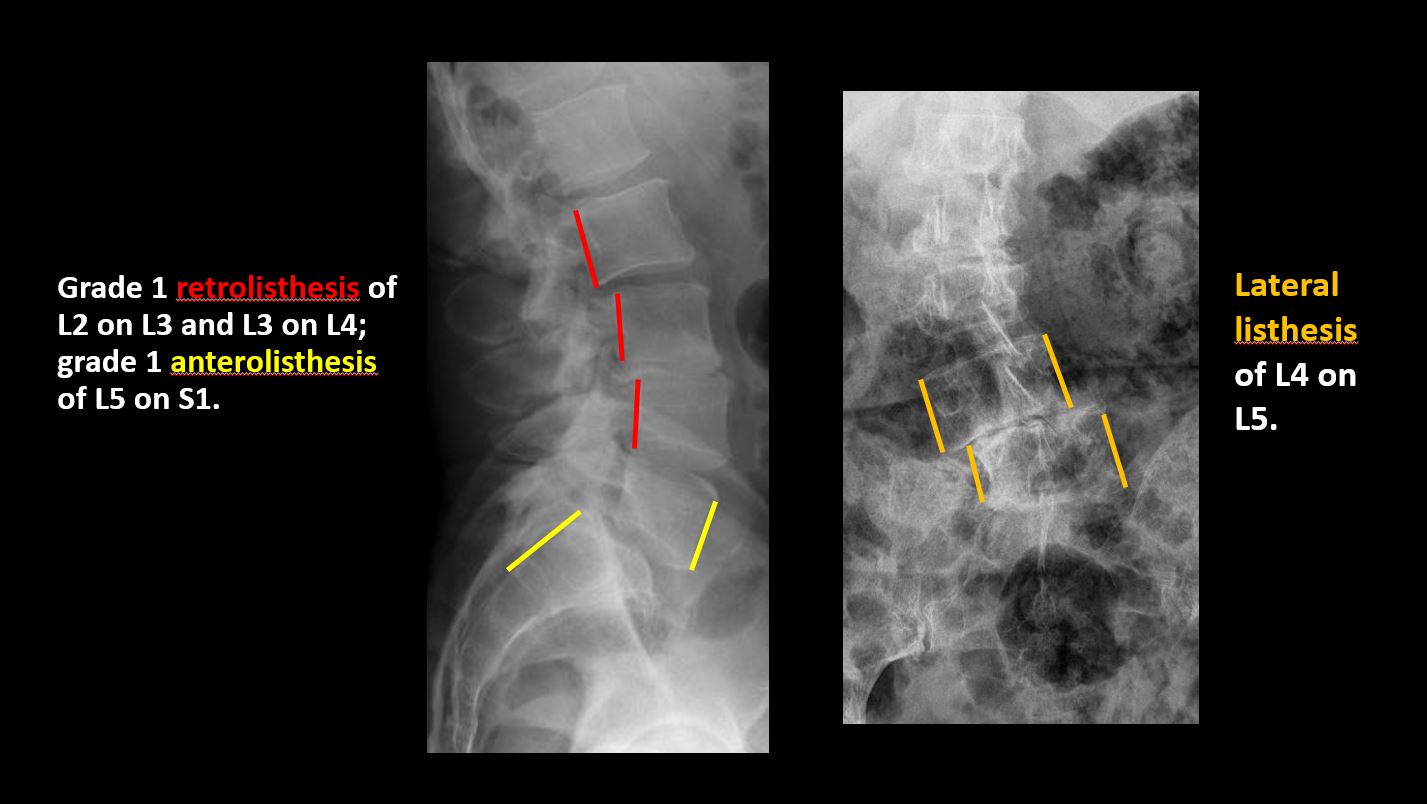

There is anterior or posterior spondylolisthesis, subluxation, or rotational abnormality at a disc space. [Yes/No]